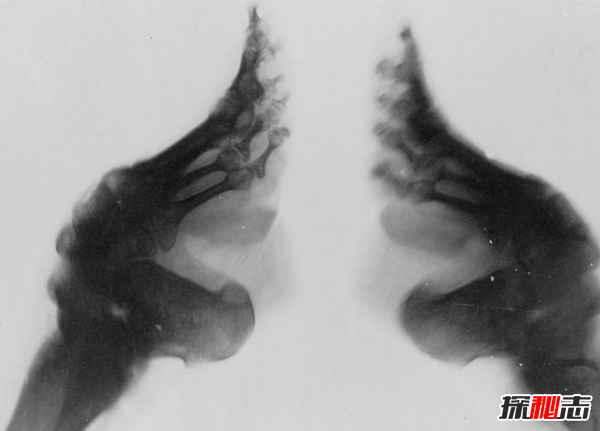

蓮花腳還導致了其他身體部位的損害,腳本身容易感染和肌肉退化,導致婦女在走路時(shí)需要幫助,無(wú)論是用拐杖還是在另一個(gè)人的幫助下。因為有蓮花腳的婦女不能正常地活動(dòng)腿,她們的步態(tài)變得傾斜,小腿的肌肉也會(huì )越來(lái)越弱,導致腿部萎縮。由于小腿無(wú)力,纏足的女性幾乎無(wú)法蹲下,這對于日?;顒?dòng)來(lái)說(shuō)是極其重要的,包括家務(wù)活、養育孩子和洗漱。

對有蓮花腳老年婦女的研究顯示,骨密度水平下降,特別是在下髖部和脊柱,這導致骨折的風(fēng)險增加。對于任何一個(gè)腳被綁住的女孩來(lái)說(shuō),最壞的情況是死亡。雖然并不是很普遍,但它確實(shí)發(fā)生了,典型的原因是感染引起的敗血癥。

除了纏足的實(shí)際痛苦之外,還有其他的醫療問(wèn)題困擾著(zhù)蓮花腳的女性。首先,腳趾甲會(huì )出現并發(fā)癥,在某些情況下,腳趾甲會(huì )在邊緣處卷曲,造成皮膚割傷甚至流血。更猖獗的是,它們會(huì )充滿(mǎn)膿液并造成極大的痛苦,腳上過(guò)多的膿會(huì )被可怕的氣味所取代。在某些情況下,腳的收縮變得嚴重,以至于皮膚和腳的部分會(huì )簡(jiǎn)單地死亡和腐爛。所有這些問(wèn)題導致高水平的感染,包括壞疽。